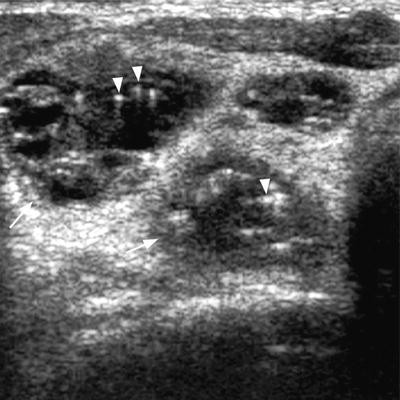

Ultrasound Of Patient S Neck Region Revealing Multiple Enlarged Lymph Download Scientific Diagram from www.researchgate.net If this happens, it is called metastasis. I had an ultrasound done in 2012 but the report for this scan never reached my previous doctor's practice and so nothing was. Ultrasound uses sound waves to create images of the body on a computer monitor. I have ocd and my obsession of 30 years is that i have a tumor on in my throat or neck. This study was done to evaluate the use of ultrasound to examine lymph nodes in the neck in surgical planning for thyroid cancer surgery and to identify which patients are best served. It can be used with a fine needle aspiration test or core biopsy test to accurately direct the tip of the needle into the lump. Some of the indications for thyroid or neck ultrasound are thyroid nodules, goiter, thyroid cancer and other neck masses. Expert ultrasound can also help confirm a diagnosis of papillary thyroid cancer which has spread to the lymph nodes of the neck.

Head and neck cancers include cancers in: There can be more than one sentinel node. I had an ultrasound done in 2012 but the report for this scan never reached my previous doctor's practice and so nothing was. This study was done to evaluate the use of ultrasound to examine lymph nodes in the neck in surgical planning for thyroid cancer surgery and to identify which patients are best served. An ultrasound of the thyroid produces pictures of the thyroid gland and the adjacent structures in the neck. While it can't diagnose cancer, it can detect the abnormal tissues that may possibly be cancerous. The image may or may not suggest cancer, but definitive diagnosis requires removal of. For most types of cancer, a biopsy is the only sure way for the doctor to know if an area of the body has cancer. When ultrasound is performed on a patient with nodular goiter, or a patient with a history of thyroid cancer, finding a prominent lymph node with a rounded shape (long/short axis ratio < 2) and absent hilar line warrants further evaluation of the node (figs. Ultrasounds have many limitations an ultrasound is not good enough for many aspects of cancer. Carotid ultrasound tests for blocked or narrowed carotid arteries, which can increase the. Confirming that a lump in the neck is developing from the thyroid or connected tissue. Spread of thyroid cancer to the lymph nodes in the neck is common and increases the risk of cancer recurrence.

Figure 3 From Post Thyroidectomy Neck Ultrasonography In Patients With Thyroid Cancer And A Review Of The Literature Semantic Scholar from d3i71xaburhd42.cloudfront.net Ultrasound is often one of the first line tests in the detection of cancer. These tests can also show whether a nodule is toxic or producing too much thyroxine, causing hyperthyroidism. Spread of thyroid cancer to the lymph nodes in the neck is common and increases the risk of cancer recurrence. I was officially diagnosed hashimoto's by my endocrinologist 2 weeks ago but she has refused to do an ultrasound of the thyroid. 8.4, 8.5, 8.6, 8.7, and 8.8). An ultrasound of the neck is used to examine the carotid arteries located on each side of a patient's neck. Our doctors also use ultrasound to check lymph nodes in the neck, where some forms of thyroid cancer can spread. It can be used with a fine needle aspiration test or core biopsy test to accurately direct the tip of the needle into the lump.

Carotid ultrasound tests for blocked or narrowed carotid arteries, which can increase the. Some of the indications for thyroid or neck ultrasound are thyroid nodules, goiter, thyroid cancer and other neck masses. Expert ultrasound can also help confirm a diagnosis of papillary thyroid cancer which has spread to the lymph nodes of the neck. It can detect abnormal tissues, growths, and cysts and give a suspicion of cancer based on how those images look. Ultrasound is widely available an is useful to identify abnormal lymph nodes that may contain cancer.

Ultrasonographic Differentiation Of Benign From Malignant Neck Lymphadenopathy In Thyroid Cancer Kuna 2006 Journal Of Ultrasound In Medicine Wiley Online Library from onlinelibrary.wiley.com But today, it is more common for a thyroid cancer to be incidentally identified on a ct/mri or neck ultrasound done for some reason unrelated to the thyroid. An ultrasound of the thyroid produces pictures of the thyroid gland and the adjacent structures in the neck. An ultrasound of the neck is used to examine the carotid arteries located on each side of a patient's neck. The mouth (oral cavity or oral cancers) the tongue. Doctors may also do tests to learn which treatments could work best. It can be used with a fine needle aspiration test or core biopsy test to accurately direct the tip of the needle into the lump. Ultrasound is relatively quick and simple test that gives very useful information about the soft tissues in the head and neck region including the lymph glands, salivary glands, thyroid gland and any abnormal lumps. The image of your thyroid and any nodules, even those you can't feel, will show up on a computer screen.

People may use the word throat to describe different parts of the neck. Your two carotid arteries are located on each side of your neck. A neck ultrasound can be used to observe the thyroid gland to look for nodules, growths, or tumors. Although many unskilled observers would believe that size is a major issue, but it actually is not. Lymph nodes are part of the lymphatic system, which helps to protect us from infection and disease. If this happens, it is called metastasis. Part of the throat (cancers of the oropharynx and tonsils, nasopharynx and hypopharynx) the nose or sinuses (nasal and sinus cancer) the salivary glands. If the person has a lump in the neck, an fna can show if the mass is from cancer spread. The expert ultrasonographer will look for multiple changes. While it can't diagnose cancer, it can detect the abnormal tissues that may possibly be cancerous. Ultrasound guidance is used to perform thyroid biopsies and improves the diagnostic accuracy of fine needle biopsy. If this lump is of concern then a biopsy would be the next step. An ultrasound of the neck is used to examine the carotid arteries located on each side of a patient's neck.